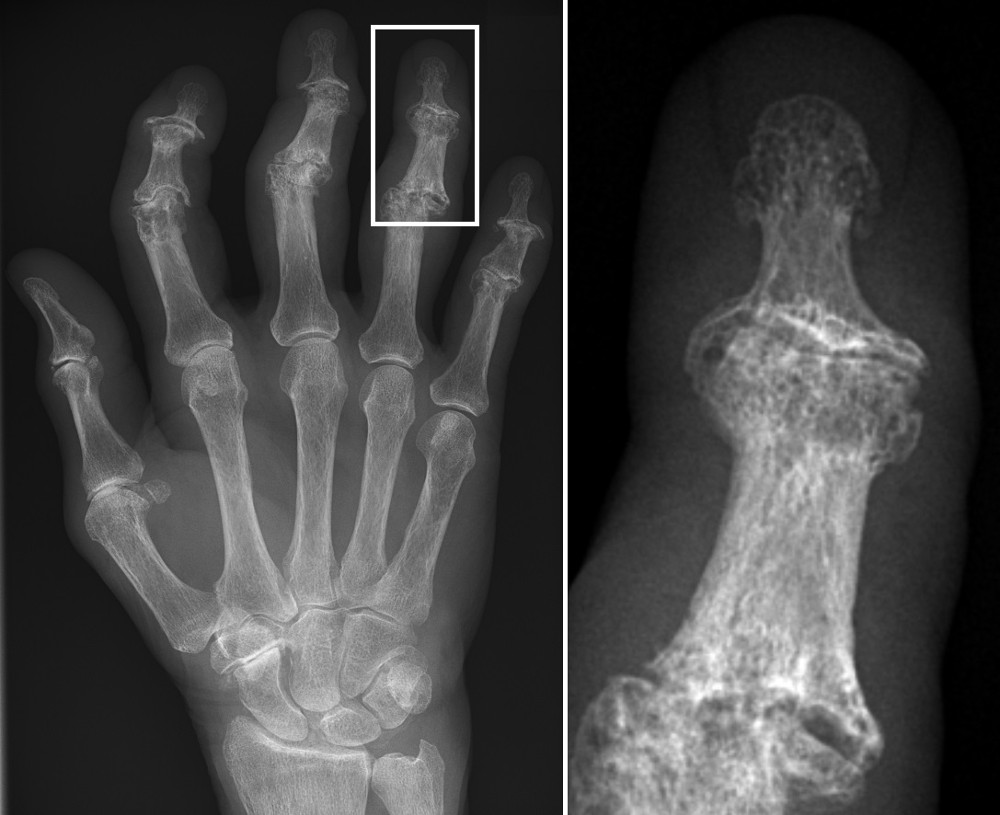

For the past couple of months, though, I’ve been bothered by pain in my hands, and after getting some X-rays and blood work, I had a conference with a kind rheumatologist yesterday at Kaiser. She showed me my X-rays on her computer screen, alongside the X-rays of a person with normal (non-painful) hands.

I could see the physical intrusions of age. The “normal” hand’s fingers had dark areas representing cushioning between the various finger segments. My cushioning was mostly worn away. The other hand’s bone segments were gracefully curved; mine were somewhat jagged in places, with what the doctor said were bone spurs.

I’m at the beginning of my journey with arthritis. It was helpful to actually see the degeneration on the screen, and hear the doctor’s explication (“moderate” in most places, “severe” in one area at the base of my right thumb). Now comes a time of looking for ways to manage the condition, to get as much of my hands’ “intuitive function” back as I can.